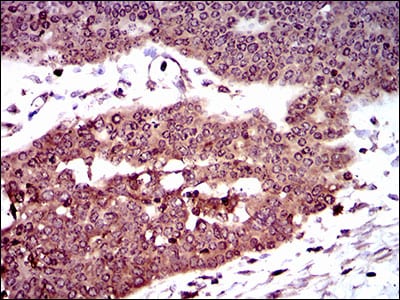

Immunohistochemical analysis of paraffin-embedded human cervical cancer tissues using MYH11 mouse mAb with DAB staining

Immunohistochemical analysis of paraffin-embedded human ovarian cancer tissues using MYH11 mouse mAb with DAB staining